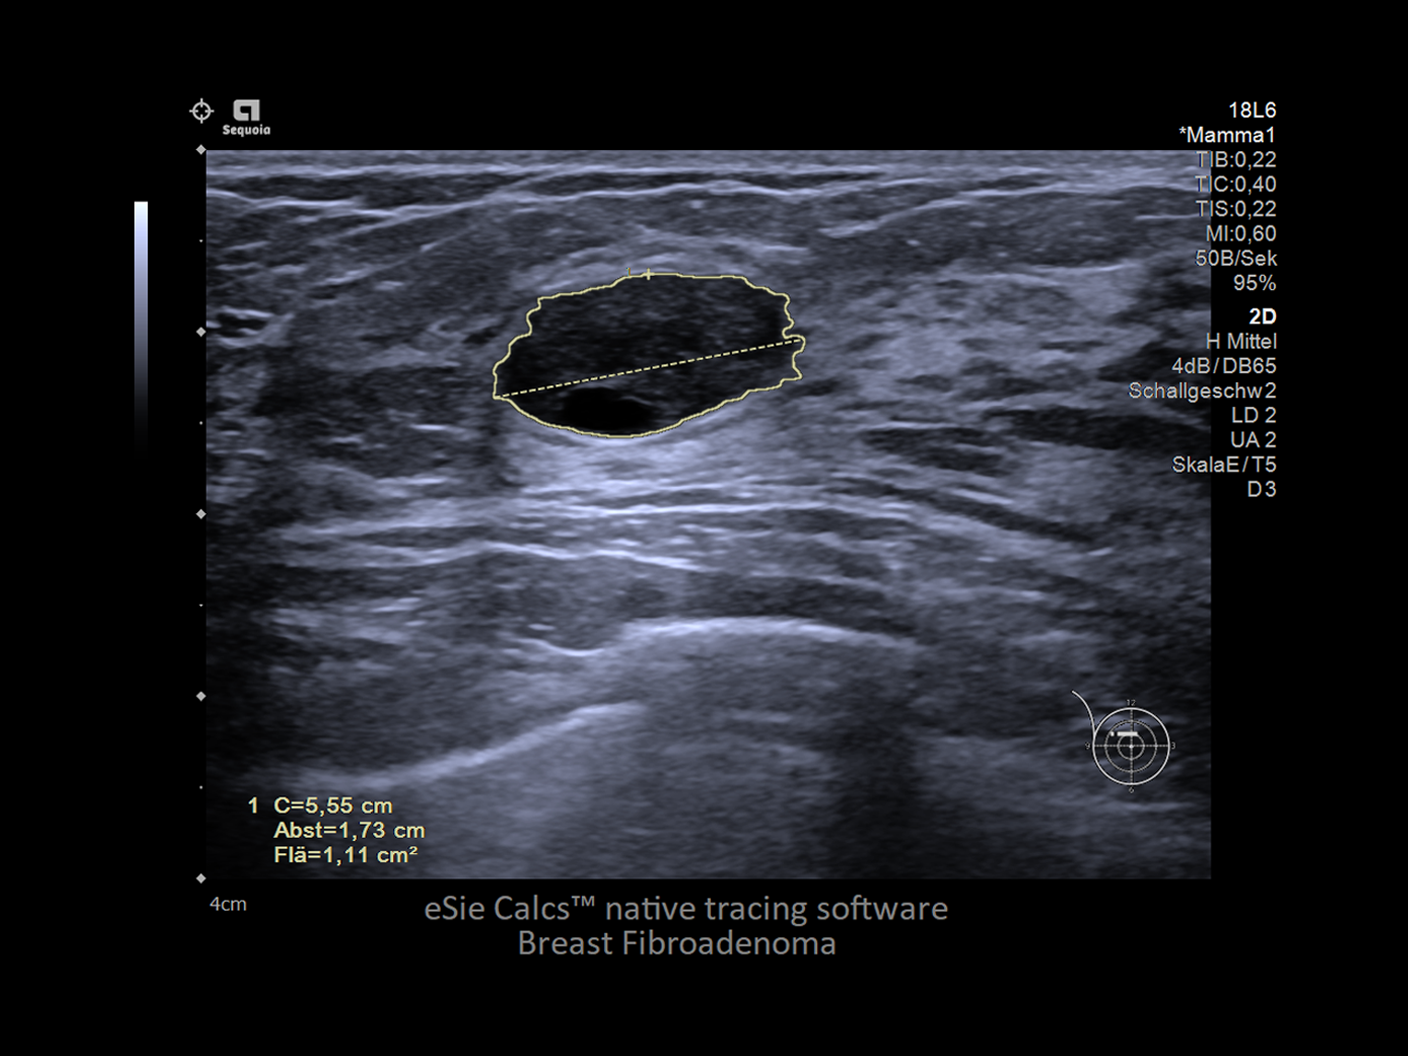

AI-powered measurement tool which provides the area, volume, diameter and length from a user-defined region of interest.